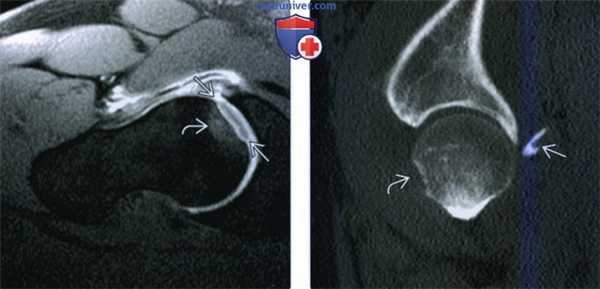

(Слева) МР-артрография, Т1 ВИ, режим подавления сигнала от жира, косой аксиальный срез: у балерины 16 лет определяется дефект хряща как спереди, так и сзади.

(Справа) МР-артрография, PDBИ, режим подавления сигнала от жира, сагиттальный срез: определяются дефекты хряща на всю его глубину в области вертлужной впадины и головки бедренной кости. Подрежающий кортикальный спой головки бедренной кости неровный. Сравните с нормальным хрящом, формирующим ободок однородной интенсивности сигнала вокруг суставных поверхностей.

(Слева) МР-артрография, PDBИ, режим подавления сигнала от жира, косой аксиальный срез: определяется смещенный костно-хрящевой осколок с уплощением головки бедренной кости и сопутствующим отеком костного мозга, что указывает на травматический коано-хрящевой перелом головки бедренной кости.

(Справа) КТ после вывиха тазобедренного суаава, сагиттальный срез: определяется небольшая коано-хрящевая вколоченная травма № передней поверхности головки бедренной кости. Утрата хряща может быть заподозрена на основании неровности кортикального слоя. Задний осколок откололся от вертлужной впадины.